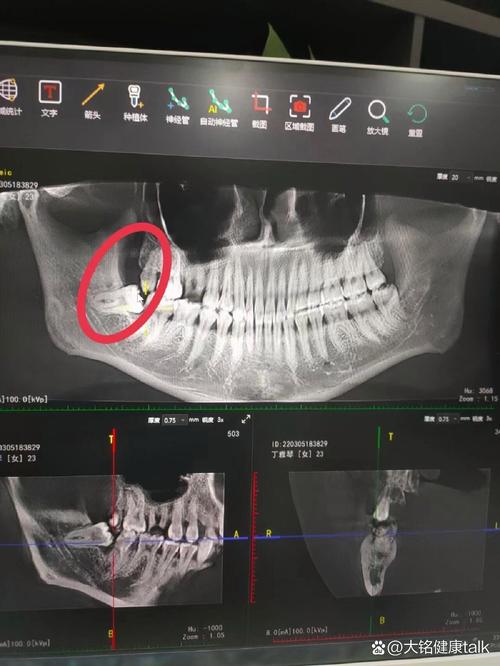

- 设备: 是否配备口腔CBCT(三维影像)?是否使用数字化口扫仪?是否有独立的种植手术室和严格的消毒灭菌流程?这些是精准种植和安全的基础。

(图片来源网络,侵删)- 全面检查: 是否进行了详细的口腔检查(临床检查、CBCT拍片、取模等)?